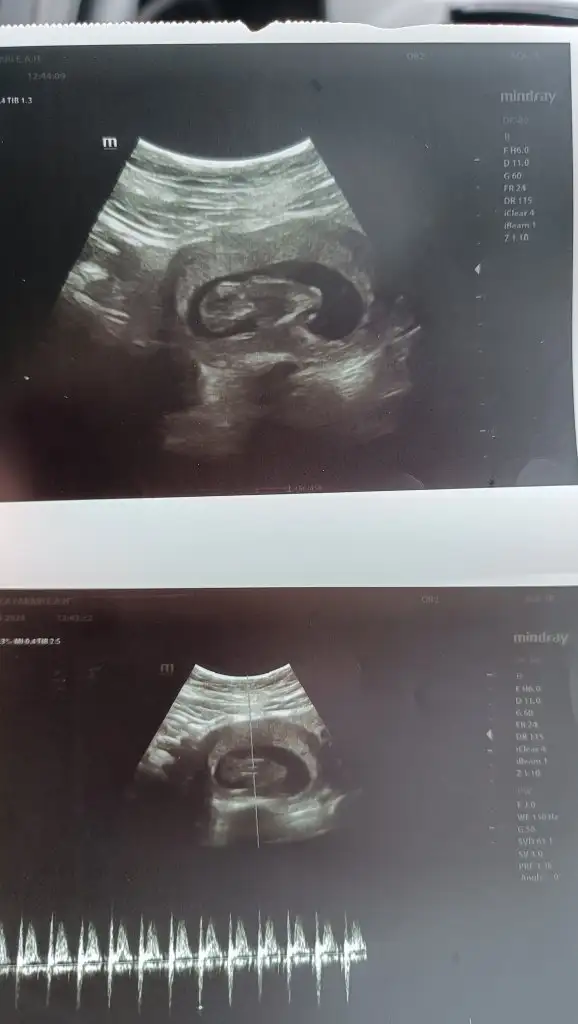

Nub teorisine göre cinsiyet tahmini yapabilen var mııı

7 haftalik 1 oğlum 2 kızım var bu 4. Supriz bir bebek tahminde bulunurmusunuz

IMG_20240425_164730.webp